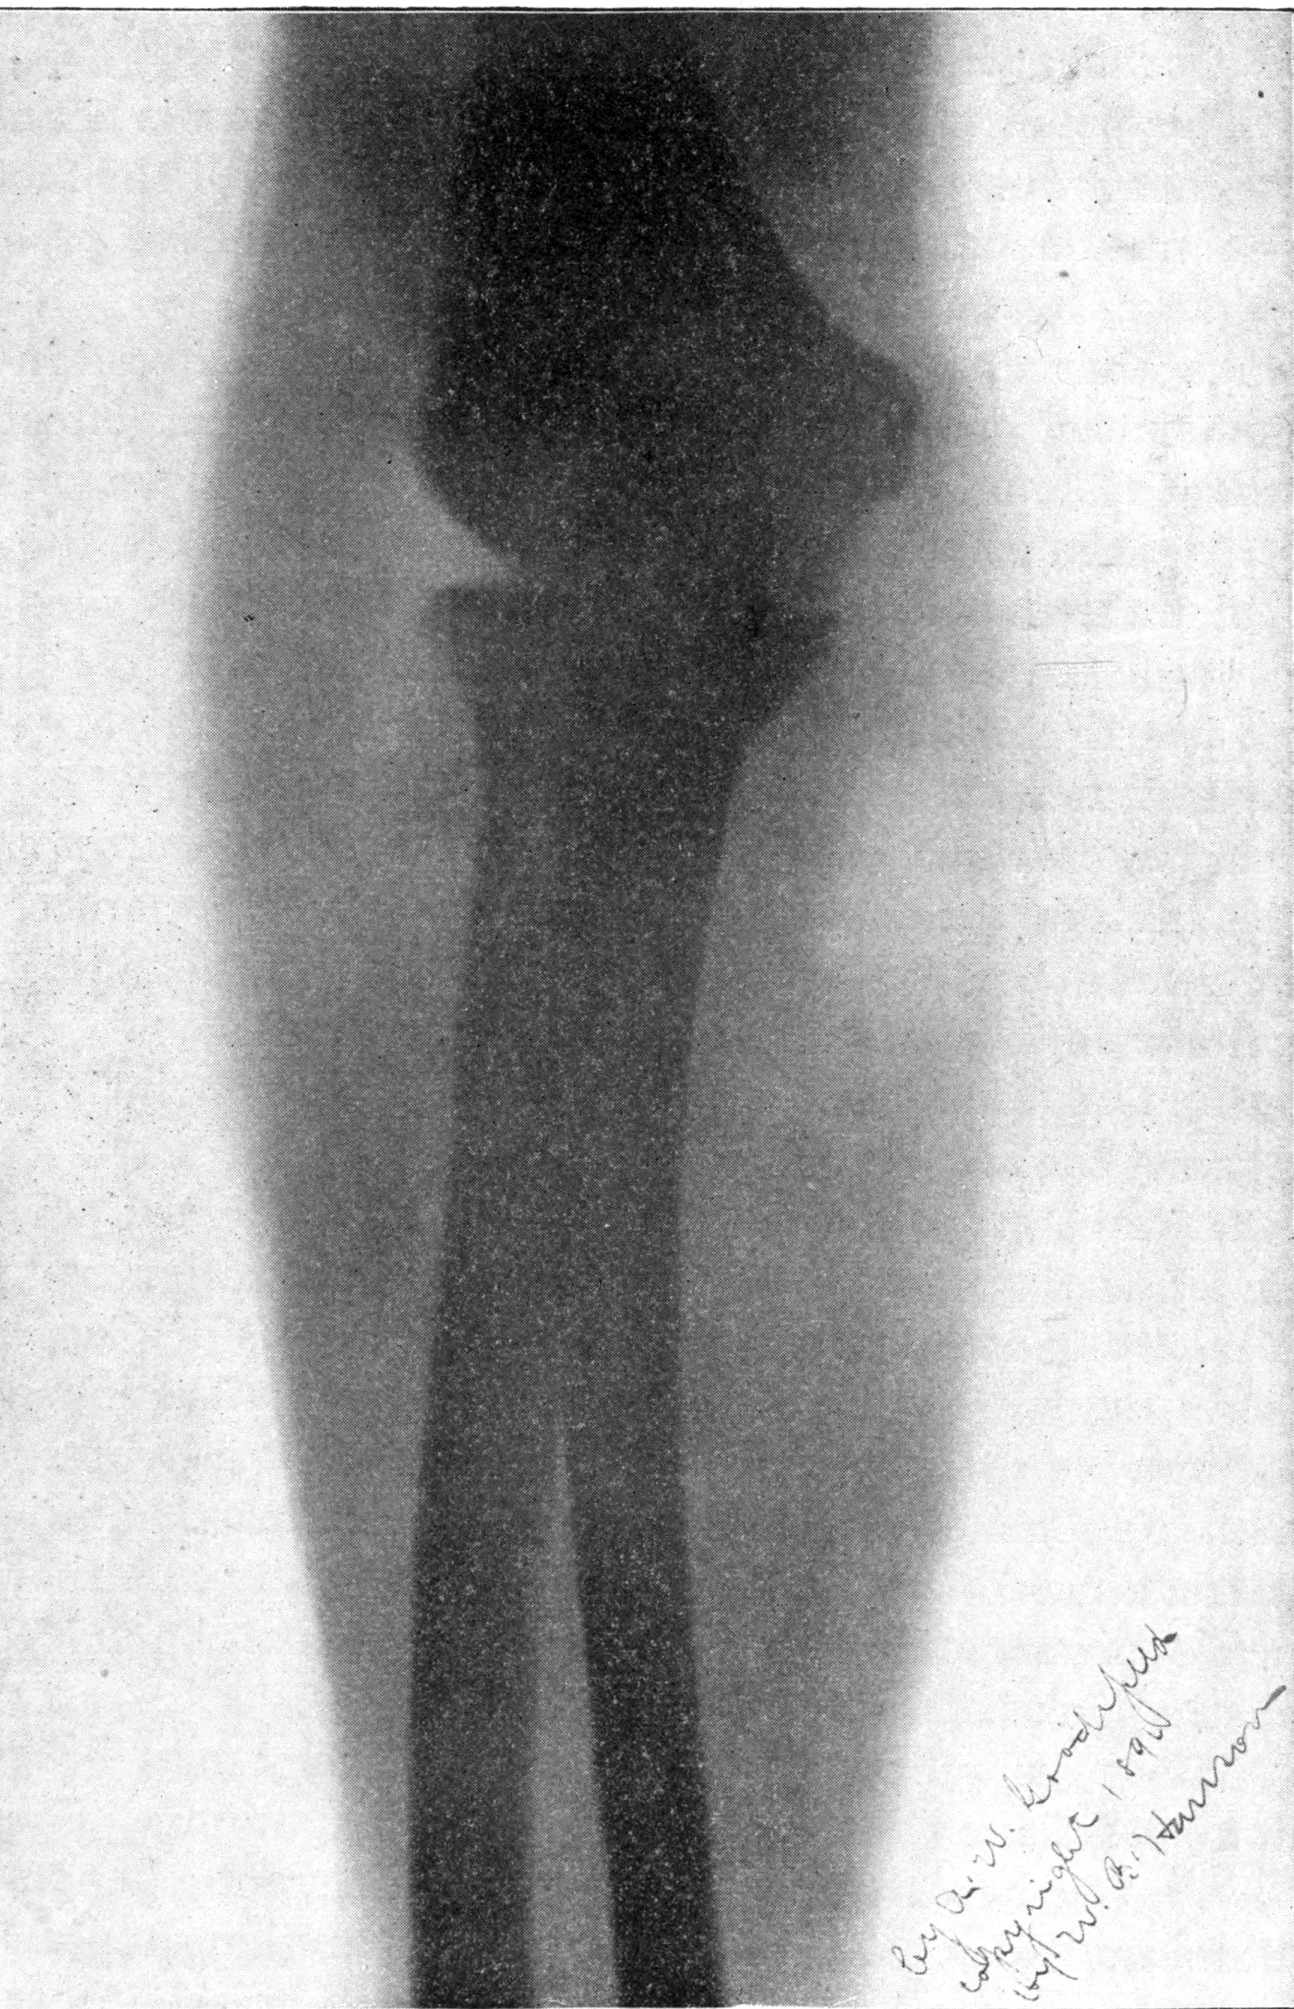

Fig. 4.—Knee, Knickerbocker Buttons, Bullet in Femur.